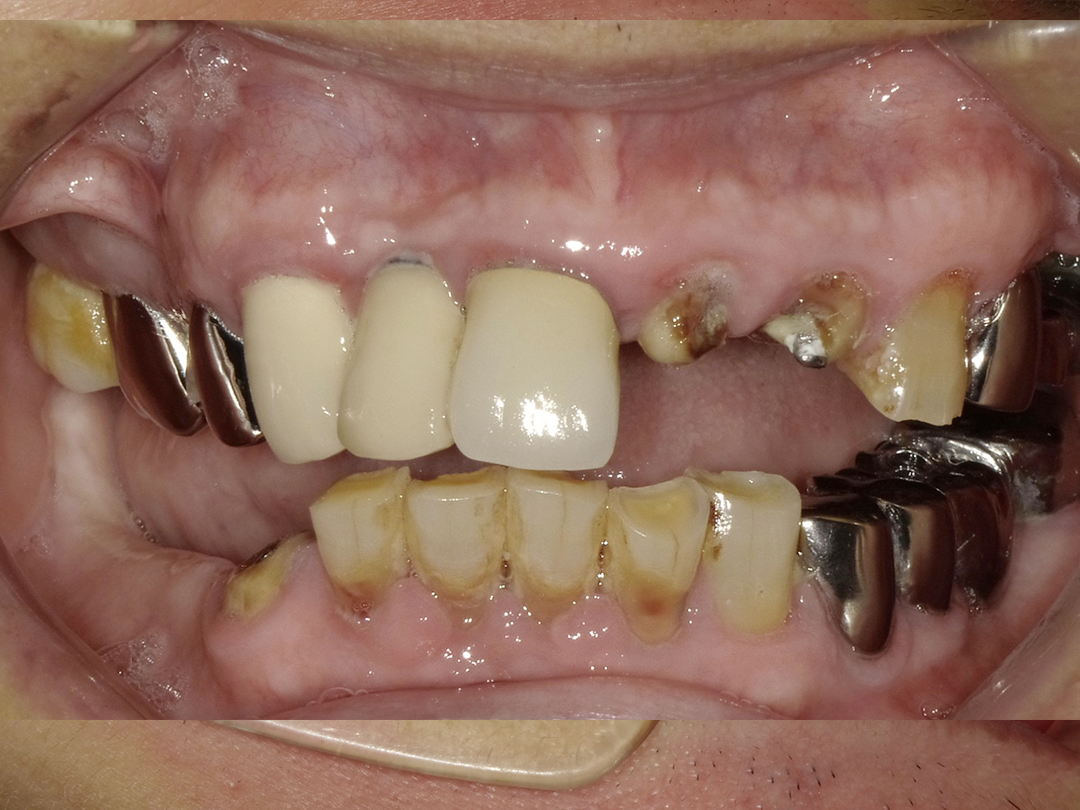

ALL ON全口重建是由4-6 顆植體(依條件而定)成,專為多顆缺牙或全口無牙患者設計的創新全口重建技術,僅需4-6 支植體即可支撐一整排固定式假牙,大幅減少手術次數與成本,並縮短療程時間。

適用無牙或重度牙周病患者